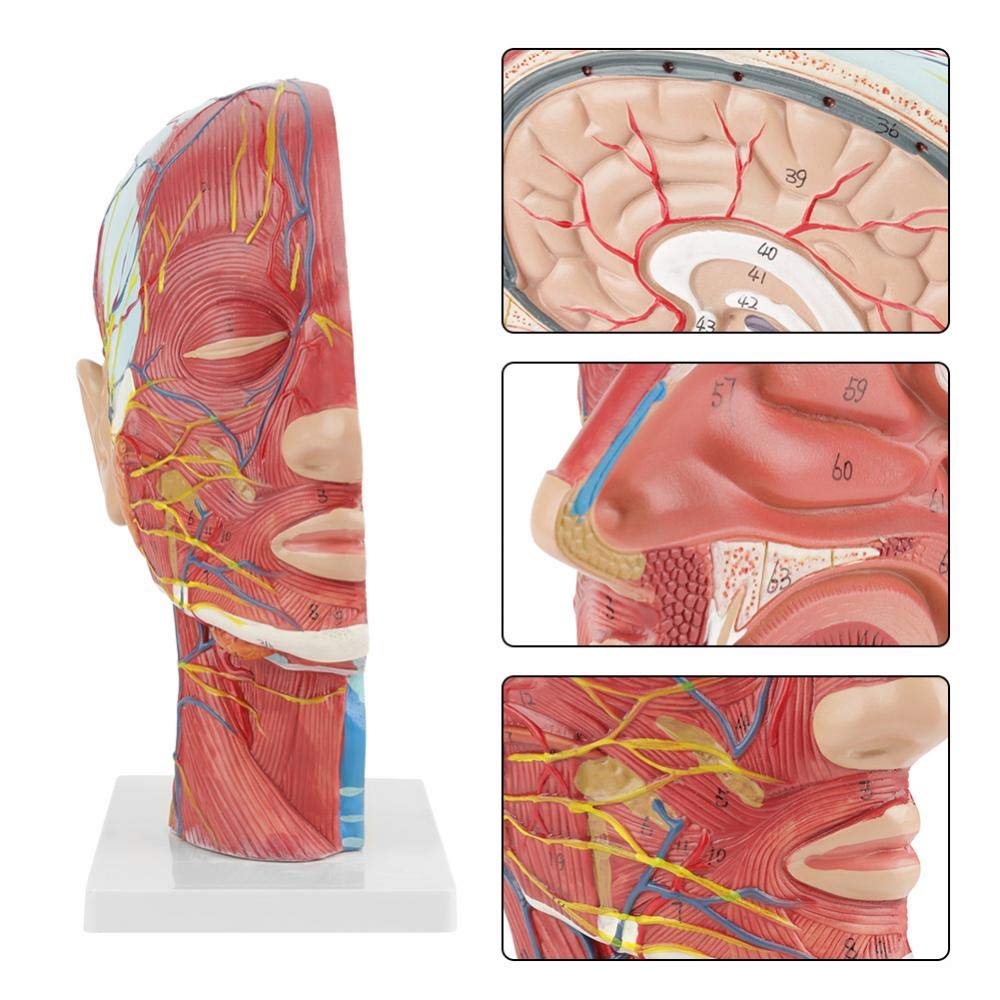

| Features | The model shows the local morphology of the inner and outer sides of the Median sagittal section of the head and neck, as well as the structures of blood vessels and nerves, and there are 84 parts indicating signs in total. |

【Superficial Neurovascular Muscle Model】Highly detailed, numbers marked, detachable ear, deepen the understanding of the superficial muscles, vessels, nerves and the internal structures of the head & neck. Red-artery, blue-vein, yellow-nerve.

【Features】It shows the superficial muscles of the exposed face; the superficial blood vessels & nerves of the face & scalp; the inner structures of parotid gland & upper respiratory tract; the sagittal cross-section structure of the cervical spine.

This model shows details of the right head neck and mid sagittal section of the human. including the superficial

muscles of the exposed face; the superficial blood vessels and nerves of the face and scalp; the inner structures

of parotid gland and upper respiratory tract; the sagittal cross-section structure of the cervical spine.

The model showed the local morphology of the medial and lateral sagittal sections of the head and neck and its vascular and nerve structures, with a total of 100 site indicators.

This model is a natural large head and neck superficial neurovascular muscle model, 1 component, showing the details of the human right head and neck and median sagittal section, including the exposed superficial muscles of the face, superficial vessels of the face and scalp, nerves and the medial structure of the parotid gland and upper respiratory tract, and the sagittal section structure of the cervical spine